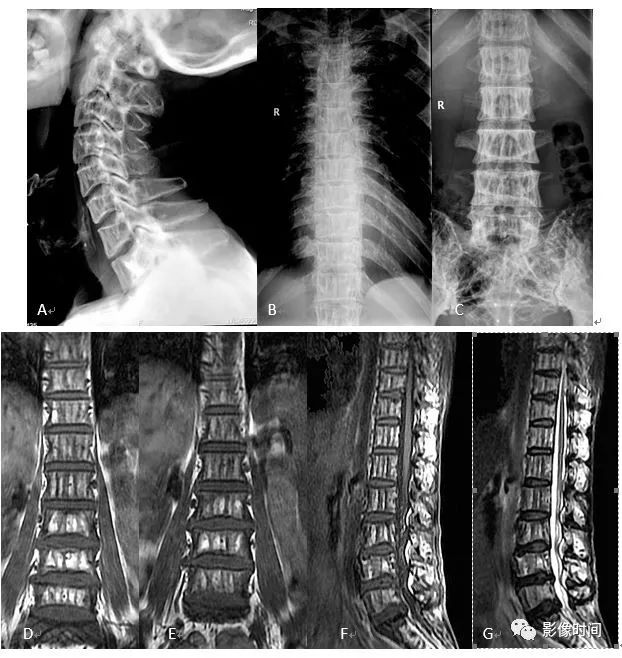

10栅栏征

栅栏征(The Palisade sign),也称灯芯绒椎体(corduroy vertebra)或灯芯绒征(corduroy sign)

脊椎椎体因病变导致骨小梁吸收、稀疏,为满足承重需要,存留的纵向骨小梁粗大;粗大骨小梁间以细条状密度减低区,形成栅栏样影像,故称栅栏征或灯芯绒椎体。

栅栏征最常见于血管瘤,以单个脊椎居多;骨质疏松如泛发性骨质增生症、老年性骨质疏松等亦可呈现此类表现,一般见于下胸椎、上部腰椎的多个椎体,只是伴有普遍的骨密度减低。有时自颈椎至腰椎全部椎体均出现栅栏征。栅栏征主要见于椎体。

典型病例

病例 1,脊柱血管瘤。胸腰椎 CT 冠状位、矢状位 MPR 重建示胸 12 椎体松质骨密度降低,其中可见粗大骨小梁呈栅栏状。

病例 2,67 岁女性,椎体血管瘤。腰椎侧位片示胸 12 及腰 3 椎体呈现栅栏征,磁共振检查证实为血管瘤。

病例 3,泛发性骨质增生症,男,47 岁。A-C.颈椎、胸椎、腰椎侧位片,显示所有椎体纵向骨小梁粗大、稀疏;粗大骨小梁间以细条状密度减低区,呈栅栏征。D-G.胸、腰椎 MR 冠状、矢状位图像,粗大、稀疏的示纵向骨小梁呈低信号,在邻近富脂肪骨髓信号衬托下呈典型的栅栏征

(引自丁香园,华夏览雄 http://radiology.dxy.cn/bbs/topic/34521015)参考文献:陈凡. 骨关节 X 线征. 武汉:湖北人民出版社,1987:94-95.